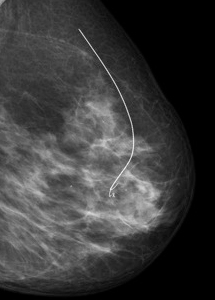

Präoperative Drahtmarkierung und Präparateradiografie

Sonografisch nicht oder nur erschwert darstellbare Befunde (z.B. Mikroverkalkungen der Brust) werden vor der Operation mit einem Draht markiert über den der Operateur die Veränderung leichter und mit geringem Gewebeschaden lokalisieren kann. Der Draht wird unter mammografischer Kontrolle über eine sehr dünne Hohlnadel (20G = 0,9mm) an den Befund herangeführt und dort mit einem Widerhaken fixiert. Zuvor werden die Haut und die darunter liegenden Gewebeschichten örtlich betäubt. Um zu Überprüfen, ob der Befund vollständig entfernt wurde, wird von dem Präparat eine Röntgenaufnahme angefertigt, eine sogenannte Präparateradiografie.